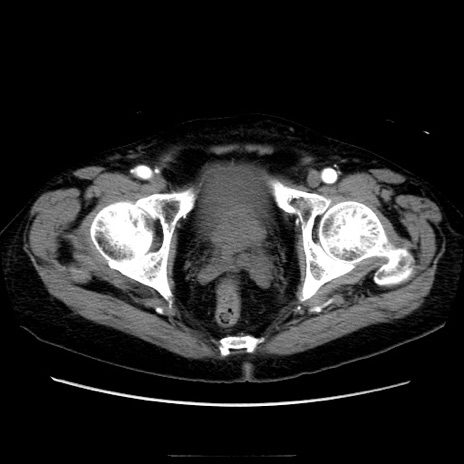

症例21(横断像)

【症例】70歳代男性

【主訴】腹痛

【現病歴】肝硬変・肝細胞癌にてかかりつけの方。約9時間前に食後より腹痛出現。症状が徐々に増悪し、嘔吐出現したため来院。

【既往歴】肝硬変、肝細胞癌(RFA、TACE後)

【身体所見】意識清明、表情苦悶様、BT 36℃、BP 129/78mmHg、P 88bpm、SpO2 97%(RA)、右上腹部から心窩部にかけて圧痛あり、反跳痛なし、筋性防御あり。

【データ】WBC 5800、CRP 0.16